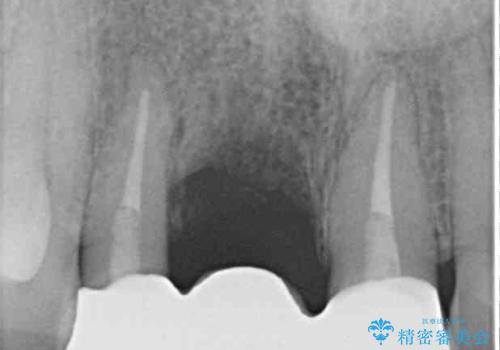

- 仮歯のまま前歯を放置しているとのことで来院された患者様です。

目視で確認できるほどしっかりとした破折が認められ、抜歯が必要と判断されました。

抜歯後は歯肉が痩せてしまうため、歯肉移植を行って歯肉の形態を改善した後、オールセラミックブリッジにて補綴することとしました。